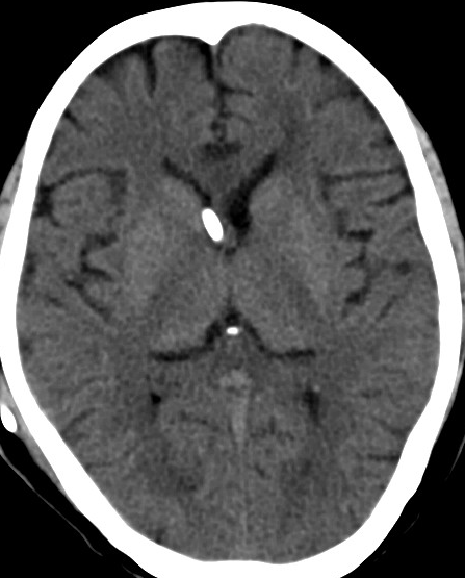

2013-8-2 CT

腰穿脑压240

2013-8-8 CT

2013-8-7 脑室腹腔分流术,初压130

2013-8-8 仍诉头痛

2013-8-10 腰穿测压150mmH2O

2013-8-12 CT

2013-8-13 调压130——150,头痛症状无明显好转

2014-2-10 CT

仍诉头痛,调压150——170

2014-3-17 CT

头痛无明显好转,调压170——190

2014-10-17 CT

仍时有前额部疼痛,程度轻,调压190—200